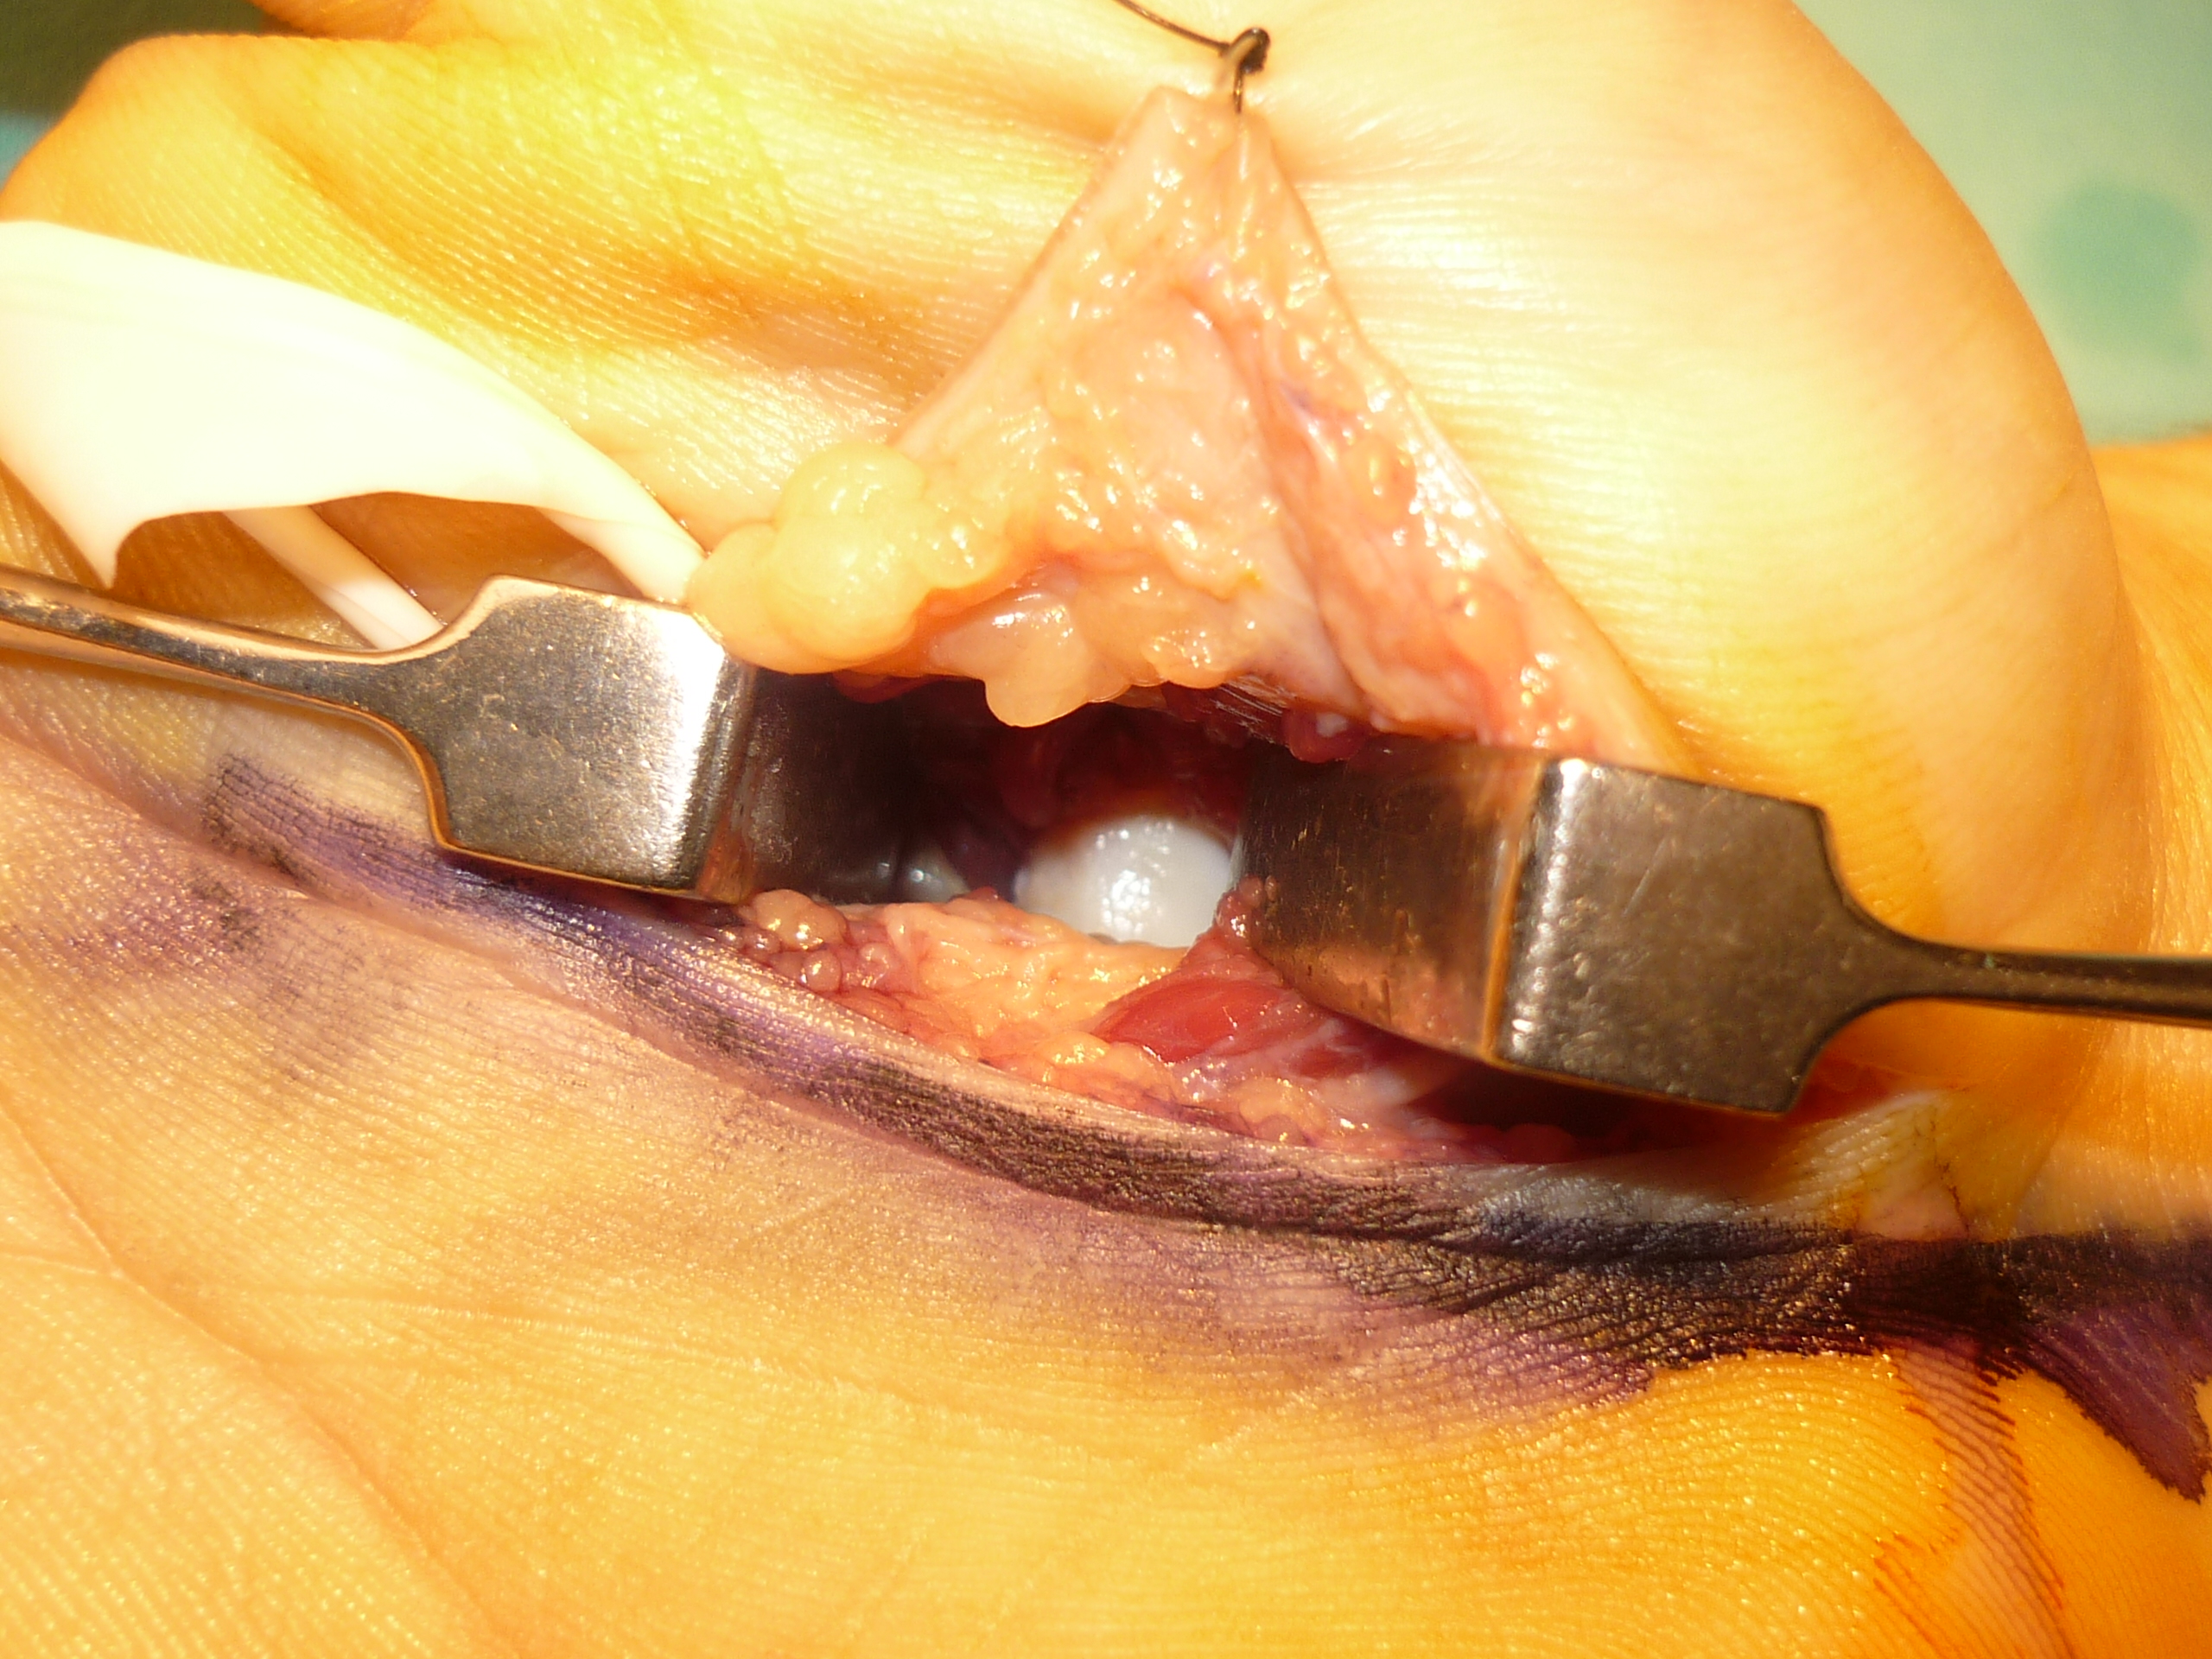

Fractura del cóndilo cubital de la base del 2do metacarpiano con desplazamiento a palmar. Presentación de un caso